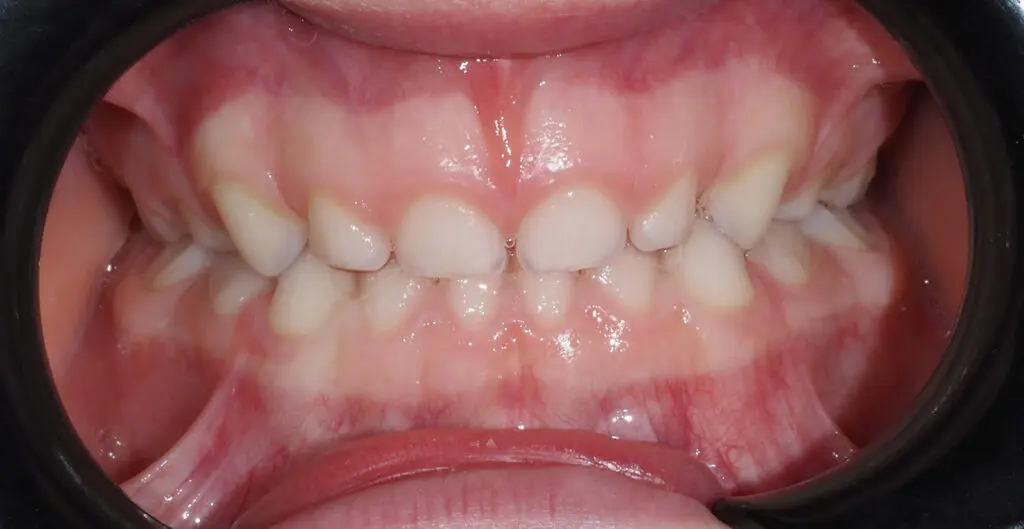

Jeśli jesteś rodzicem kilkulatka, który jakoś tak szybko się męczy, w nocy wierci się niemiłosiernie, chrapie i sapie. Może często ma otwartą buzię, w której z dumą obserwujecie równiutkie, bielutkie ząbki, ustawione idealnie jeden przy drugim? O! jak tutaj!

No czym się tu martwić? Piękny uśmiech! Niby tak, ale ten pacjent ma już 5 lat. W szczęce i żuchwie trwa intensywny proces zanikania korzeni mlecznych siekaczy i wychodzenia stałych. Tak powinno być, ale jeśli miejsca jest zbyt mało, stałe zęby nie spieszą się do wychodzenia. W wielu gabinetach rodzic usłyszy, żeby przyszli, jak wyjdą szóstki i siekacze.

PRZED